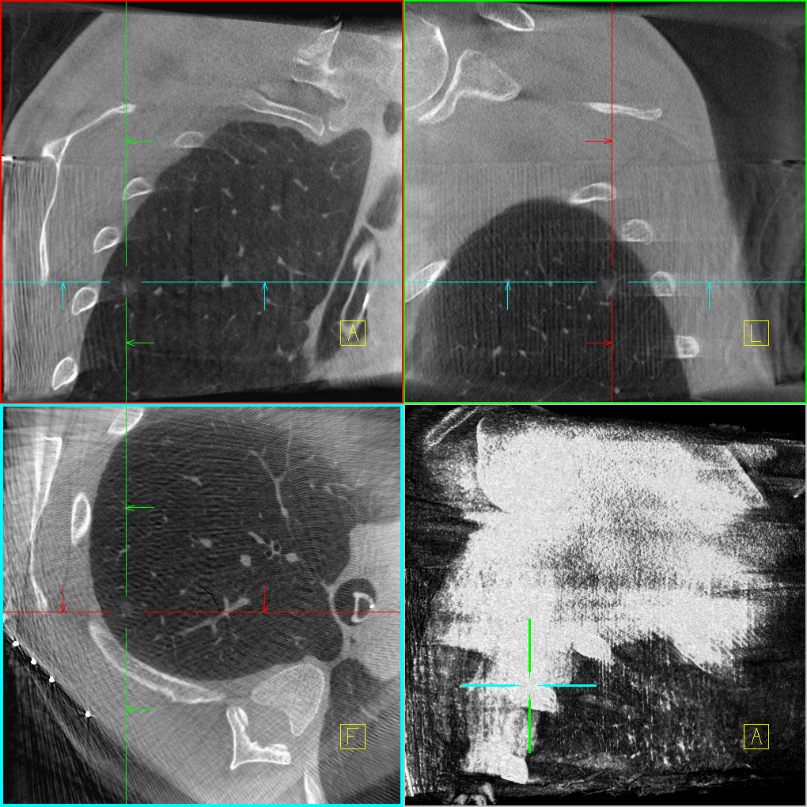

定位前扫描三维

激光导航定位